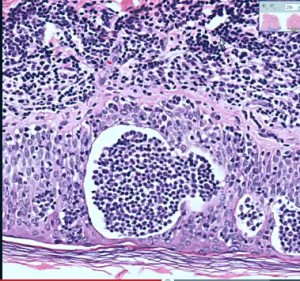

- Tumors: As mycosis fungoides is a type of lymphoma, its most important indicators are tumors as well as the presence of other abnormalities in other regions of the body. However, one should note that even biopsies of the tumors may not reveal or diagnose the presence of the condition and hence they should be considered only as a warning sign of mycosis fungoides.

- Lesions: Lesions caused due to mycosis fungoides can be very damaging to the skin. One can properly diagnose the condition by taking biopsies of the skin lesions and then testing them for the presence of lymphoma-like cells. In case, the lesions remain untreated, they can rapidly spread to other areas of the body and develop into nasty ulcers and sores. Hence, such lesions should be immediately checked by a doctor.

Mycosis Fungoides pictures